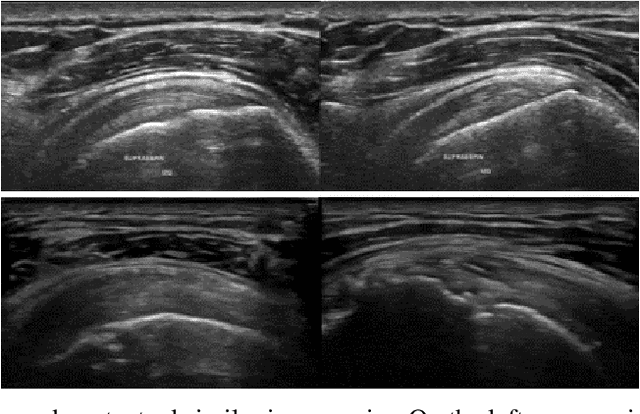

Abstract:The use of synthetic images in medical imaging Artificial Intelligence (AI) solutions has been shown to be beneficial in addressing the limited availability of diverse, unbiased, and representative data. Despite the extensive use of synthetic image generation methods, controlling the semantics variability and context details remains challenging, limiting their effectiveness in producing diverse and representative medical image datasets. In this work, we introduce a scalable semantic and context-conditioned generative model, coined CSG (Context-Semantic Guidance). This dual conditioning approach allows for comprehensive control over both structure and appearance, advancing the synthesis of realistic and diverse ultrasound images. We demonstrate the ability of CSG to generate findings (pathological anomalies) in musculoskeletal (MSK) ultrasound images. Moreover, we test the quality of the synthetic images using a three-fold validation protocol. The results show that the synthetic images generated by CSG improve the performance of semantic segmentation models, exhibit enhanced similarity to real images compared to the baseline methods, and are undistinguishable from real images according to a Turing test. Furthermore, we demonstrate an extension of the CSG that allows enhancing the variability space of images by synthetically generating augmentations of anatomical geometries and textures.